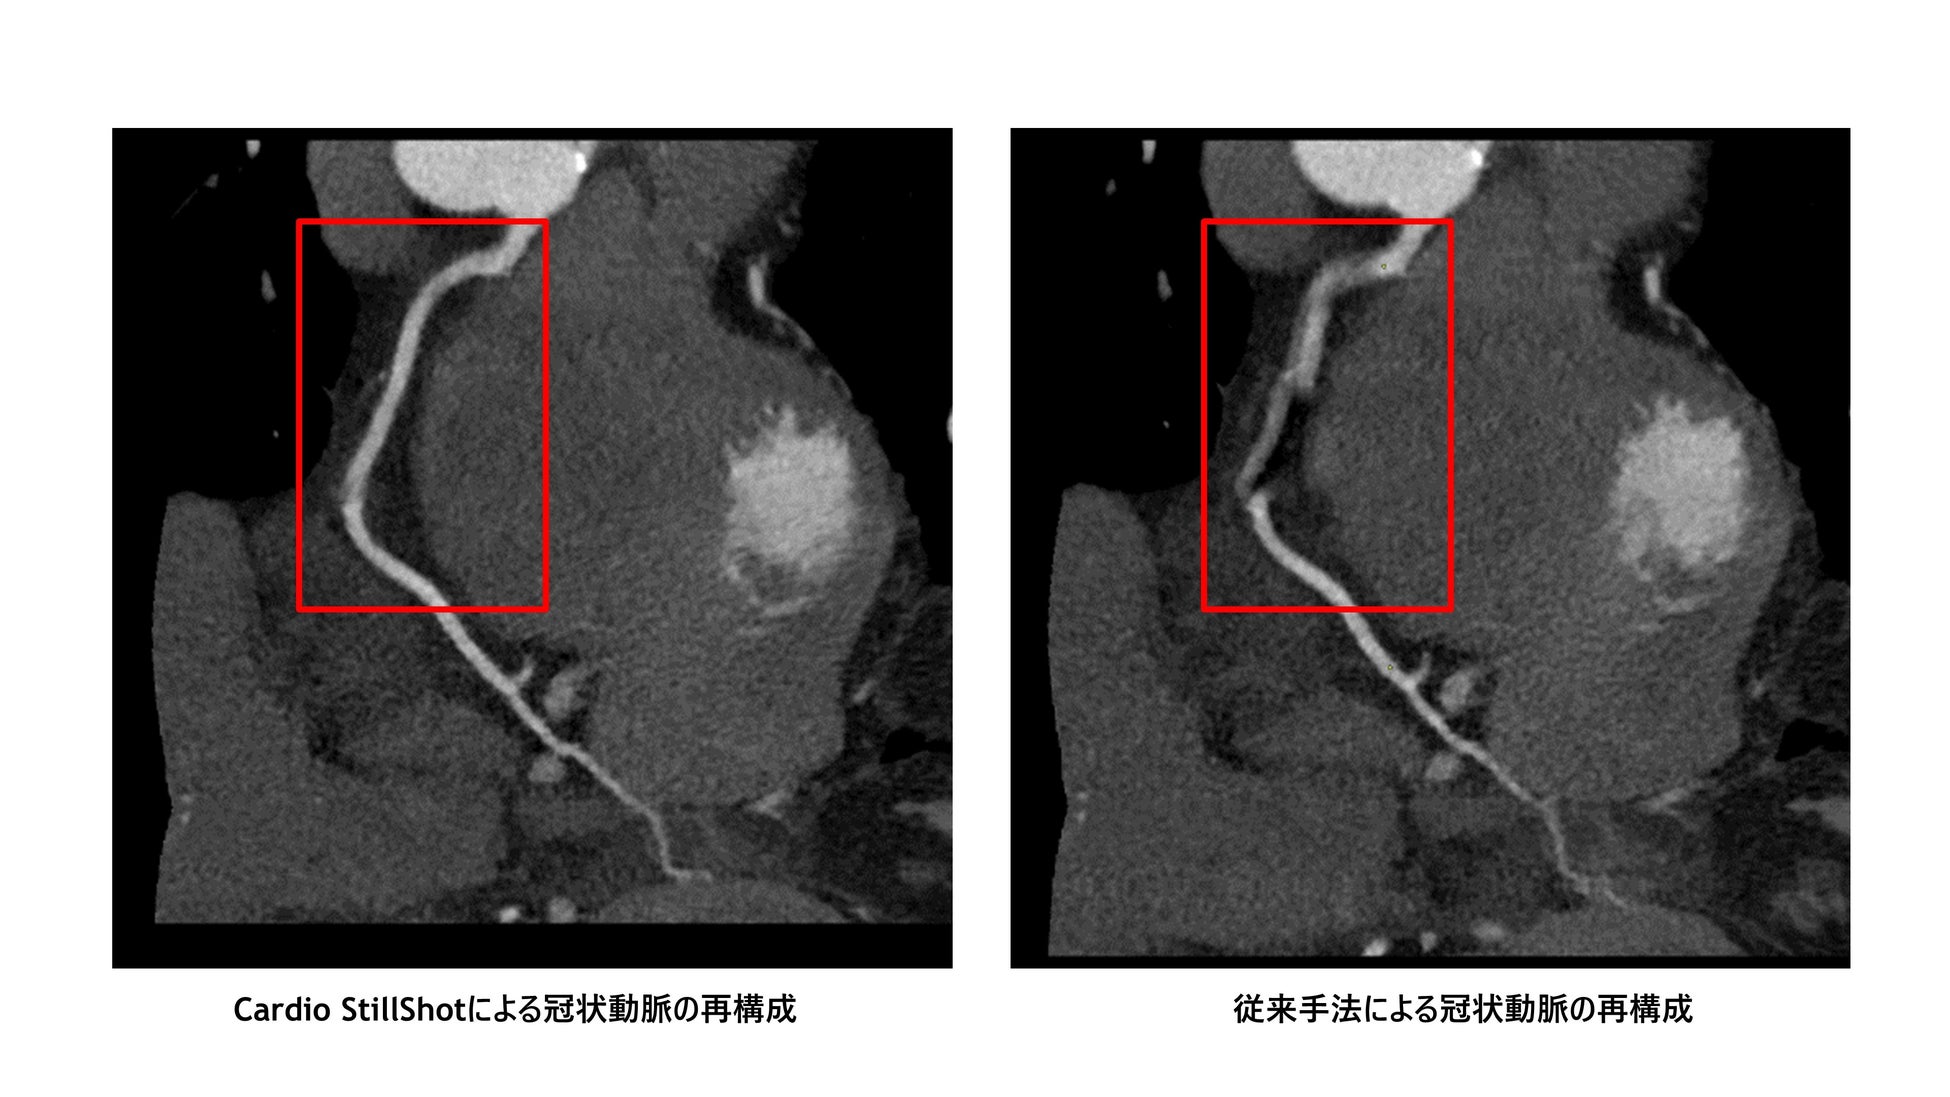

従来の同社のCT装置で冠動脈を撮影する場合、X線管が一回転するのに0.35秒かかり、時間分解能としてはその半分の時間である175ミリ秒でした。これに対し、Cardio StillShotは運動ベクトル フィールドによる補正を用いた画像再構成により、実効時間分解能としては最大28ミリ秒を達成しました。175ミリ秒から比較すると、6.25倍の時間分解能の改善を達成しています。Cardio StillShotは血管だけでなく、大動脈弁や心筋などに対しても効果を発揮します。

Cardio StillShotにより、臨床現場における、撮影後に最良の再構成タイミングを探す時間の短縮が期待されるほか、動きによるブレの少ない画像が提供できるため、診断能の向上にも貢献します。将来的には心臓CT検査で使用する心拍数を下げる薬(βブロッカー)の投薬を不要にし、患者の負荷を減らすことも視野に入れています。現在は心臓、特に冠動脈、心筋、弁が再構成の対象となっていますが、心臓以外の部位への展開も検討されています。